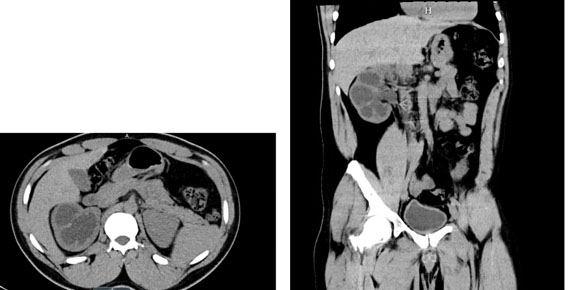

A 34-year-old male was referred for incidental right hydronephrosis observed on a CT abdomen and pelvis after a motor vehicle collision. The patient reported right flank pain following the accident. Past medical history and past surgical history were unremarkable. The patient denied hematuria, dysuria, lower urinary tract symptoms, or a history of urinary tract infections. Right costovertebral angle tenderness was present on physical examination. Urinalysis and urine culture were negative. Serum creatinine was 1.17 mg/dL, down from a previous measurement months before the motor vehicle accident of 1.77 mg/dL. A CT urogram revealed severe right hydronephrosis with possible ureteropelvic junction obstruction and diffuse thinning of the right renal parenchyma (Figure 1A and Figure 1B). A diuretic renogram was then obtained due to the thinning of the renal parenchyma and an unknown duration of hydronephrosis on the right kidney. There was a concern that the renal function may have declined over time due to prolonged obstruction. Subsequent diuretic nuclear renogram demonstrated normal uptake and a dilated right renal collecting system with delayed response to Lasix consistent with right partial high-grade obstruction (t1/2 25 minutes) (Figure 2). We then proceeded with cystoscopy with right retrograde pyelography to better detail the origin of the obstructive process. This demonstrated a tortuous proximal ureter with medial deviation and severe hydronephrosis consistent with a retrocaval ureter (Figure 3). The additional investigation using a retrograde pyelogram was performed for better diagnostic testing in case of future intraoperative planning for correction of the ureter. The retrograde pyelogram added details on the course of the proximal ureter and its’ anatomical tortuosity. A ureteral stent was placed for symptomatic relief of obstruction. The patient elected to undergo right robotic-assisted laparoscopic ureteroureterostomy. The patient was given prophylactic antibiotics. He was placed in the left lateral decubitus position with table flexion. Standard 8 mm da Vinci Xi (Intuitive Surgical, Sunnyvale, CA) trocar placement was performed for a right renal procedure (Figure 4). The robotic portion began with medial reflection the hepatic flexure and exposure of the right renal pelvis in standard fashion. The renal pelvis was expectedly dilated and prominent. The proximal ureter and IVC were identified. The ureteropelvic junction was dissected and encircled with a vessel loop. The ureter was found to be coursing posterior to the IVC, confirming retrocaval ureter. Identification of the ureter distal to the level of obstruction on the medial side of the IVC in the interaortocaval space was conducted (Figure 5). The distal aspect of the ureter was isolated with a second vessel loop. Care was taken not to unduly devascularize the ureter while mobilizing it to the extent allowing for transection and transposition of the ureter ventral to the IVC. The proximal ureter was sharply transected just distal to the ureteropelvic junction. The previously placed ureteral stent was removed. The ureter was transposed anterior to the IVC without tension (Figure 6). The proximal and distal ends of the ureter were spatulated, and a standard ureteroureterostomy was performed with two running stitches of 4-0 PDS suture (Ethicon, Bridgewater, NJ). Prior to completion of the ureteral anastomosis, a new 6 French, 28 cm double-J ureteral stent was then advanced antegrade over a Sensor wire (Boston Scientific, Marlborough, MA). The proximal stent coil was placed into the renal pelvis, and the anastomosis was completed. A JP drain was placed, and a Foley catheter was kept indwelling.

Figure 1: (A) Axial, (B) Transverse. Cross-sectional imaging on initial presentation showing severe hydronephrosis with possible ureteropelvic junction obstruction from an abrupt transition point at the right ureteral pelvic junction.